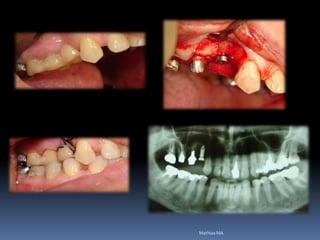

Ausência ou perda dental x implantes

Periodonto íntegro               perdas de suporte

Atrofias ósseas x implantes

Procedimentos reconstrutivos       Compensação protética

prognóstico

favorável                        desfavorável

•Áreas de interesse implantar

Perdas dentárias , tecido ósseo e tecido mucoso